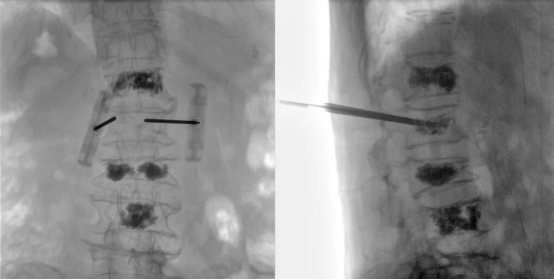

Recently, with the assistance of the Perlove Medical's all-in-one FPD C-arm, a hospital successfully performed a multi-segment percutaneous kyphoplasty (PKP).

The Perlove Medical All-in-One C-arm with a Large Flat Panel Detector features a 30 cm × 30 cm field of view, allowing a single exposure to cover the entire affected vertebral region.

This enables surgeons to comprehensively observe the injured and adjacent vertebrae at once, without repeated positioning or multiple exposures.

It enhances surgical efficiency and accuracy, while reducing the patient’s radiation dose throughout the procedure and saving valuable operation time.

■ High-Definition Imaging for Precise Surgical Guidance

Imaging quality is critical to the surgical success. The system adopts advanced imaging technology that effectively minimizes signal conversion loss, geometric distortion, and brightness non-uniformity. Through a fully digital imaging system, it enables a high-quality and efficient workflow covering image acquisition, transmission, post-processing, and storage — providing clear and accurate imaging support for precise surgical operations.